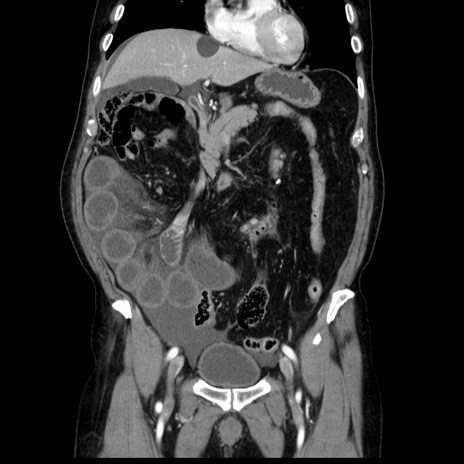

症例30(冠状断像)

【症例】80歳代男性

【主訴】臍周囲痛

【現病歴】約6時間前から臍下部痛が出現。次第に腹部膨隆・背部痛も生じてきたため来院。背部痛の場所は変化しない。

【既往歴】腎盂腎炎

【身体所見】意識清明、BT 36.3℃、BP  131/87mmHg、P 87bpm、SpO2 100%(RA)、臍周囲自発痛・圧痛あり、反跳痛なし、自発痛部位に一致して板状硬あり、腹部膨隆、腸雑音減弱、CVA tenderness両側陰性。

【データ】WBC 19600、CRP 0.33